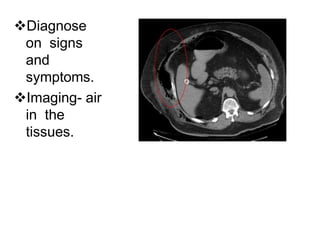

Diagnose

on signs

and

symptoms.

Imaging- air

in the

tissues.